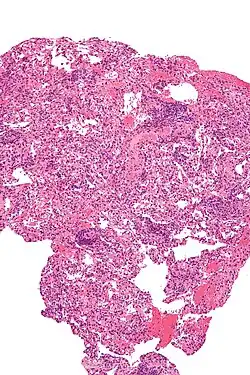

Chronic rejection, meaning repeated bouts of rejection symptoms beyond the first year after the transplant surgery, occurs in approximately 50% of patients.[33] Such chronic rejection presents itself as bronchiolitis obliterans, or less frequently, atherosclerosis.[33]